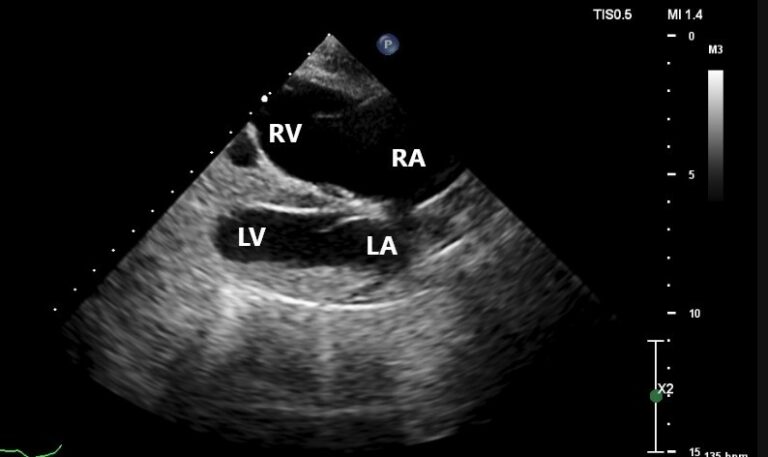

Echocardiogram via consultation with Cardiology Service

» Normal left-sided chamber dimensions » Moderate right atrial enlargement » Marked right ventricular enlargement » Slightly thickened mitral valve with mild mitral regurgitation » Mildly thickened tricuspid valve with severe tricuspid regurgitation » » Regurgitation velocity 2.39 m/s (pressure gradient 23 mmHg, estimating normal systolic pulmonary arterial pressure)

» Mild pulmonary insufficiency (end-diastolic velocity 1.57 m/s [pressure gradient 10 mmHg, estimating normal diastolic pulmonary arterial pressure]) » ECG during echocardiogram indicated sinus rhythm with occasional VPCs in isolation

RA=right atrium; RV=right ventricle; LA= left atrium; LV=left ventricle